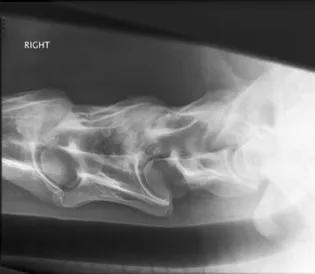

Radiograph

Radiographs showing arthropathy of caudal cervical facet joints causing spinal cord compression.